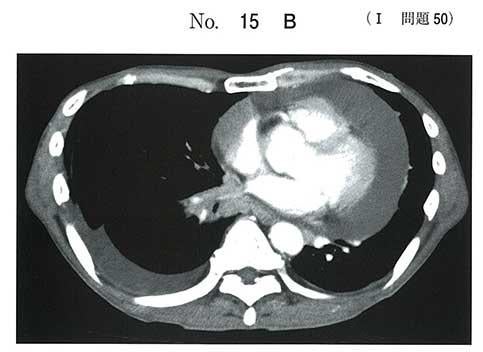

画像はすっごく派手で、びっくりします!

これって、何mL位溜まってるんでしょうかねぇ…